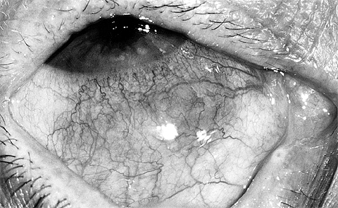

Staphyloma results from bulging of the uvea into ectatic sclera. It may be anterior, equatorial, or posterior. Anterior staphylomas are generally located over the ciliary body (ciliary staphyloma) (Figure 7-10) or between the ciliary body and the limbus (intercalary staphyloma). Equatorial staphylomas are located at the equator and posterior staphylomas posterior to the equator. Posterior staphylomas are most commonly seen near the optic nerve head. Patients with posterior staphyloma generally have poor vision and high myopia, though cases of congenital peripapillary staphyloma in patients with normal or nearly normal vision have been reported. Posterior staphyloma usually produces choroidal atrophy and may be associated with subretinal neovascularization. Staphyloma must be differentiated from extreme myopia and central coloboma of the optic nerve head.

Figure 7-10

Figure 7-10: Ciliary staphyloma. (Courtesy of P Thygeson.)